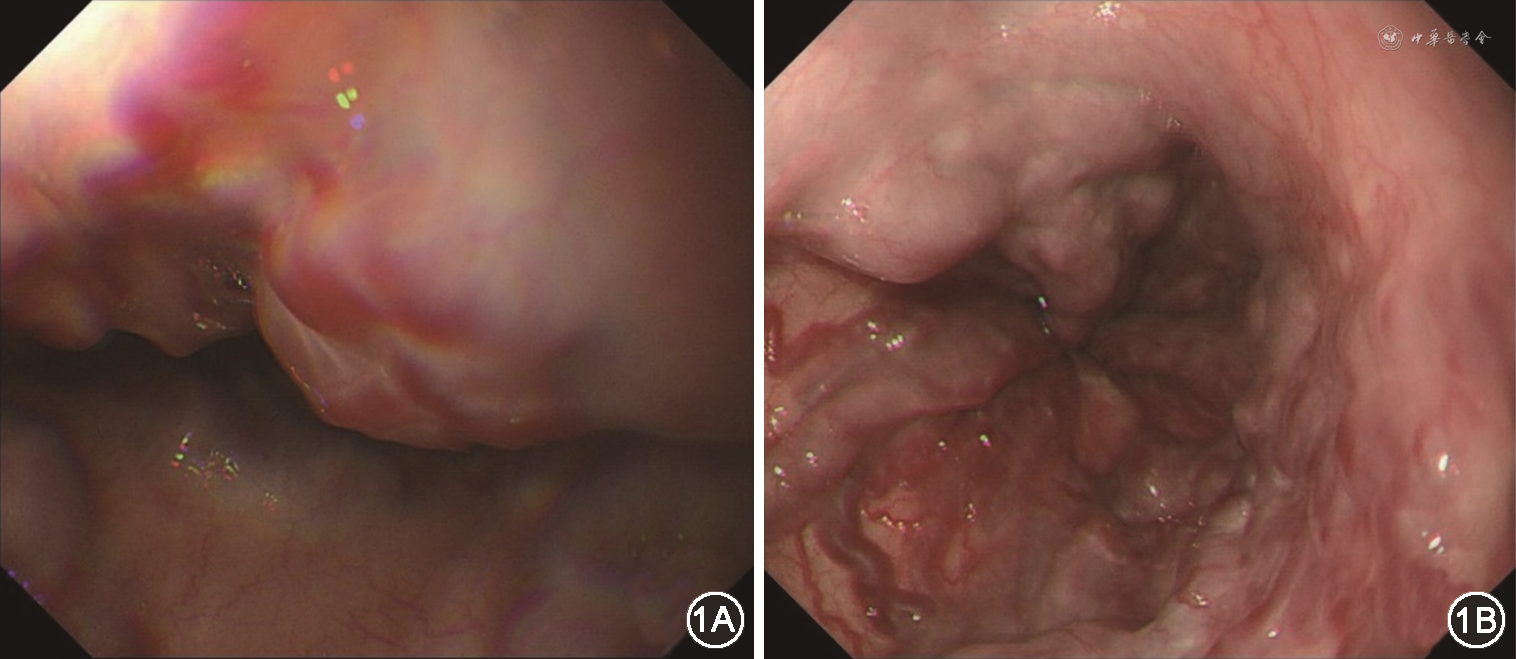

入院后检查:血WBC 15.7×109/L,中性87%,淋巴7%,Hb 82 g/L,PLT 391×109/L。ALB 29 g/L,丙氨酸转氨酶(ALT)、天冬氨酸转氨酶(AST)正常,碱性磷酸酶(ALP)166 U/L,γ-谷氨酰转移酶(GGT)72 U/L;降钙素原(PCT)2~10 μg/L;PT 14.4 s,APTT 37.9 s,INR 1.31;粪便OB(+)。腹部CT及MRI示肝脏弥漫性病变、脾大、腹水(图2、3)。立位腹平片可见左侧近中线处小肠扩张,未见明显液平,符合小肠不全梗阻表现(图4)。